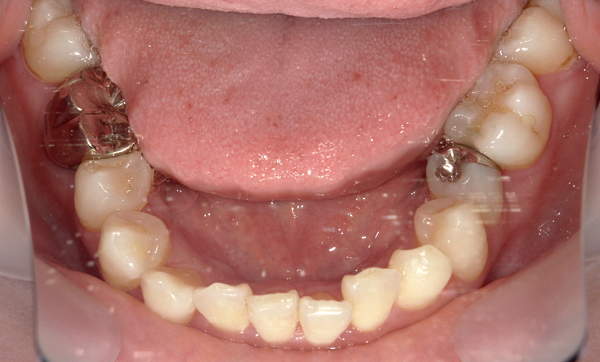

症例_008 「上下の前歯」症例

治療期間:13ヶ月金額:57万円+税40代女性捻転歯前歯のガタガタ

Before | After |